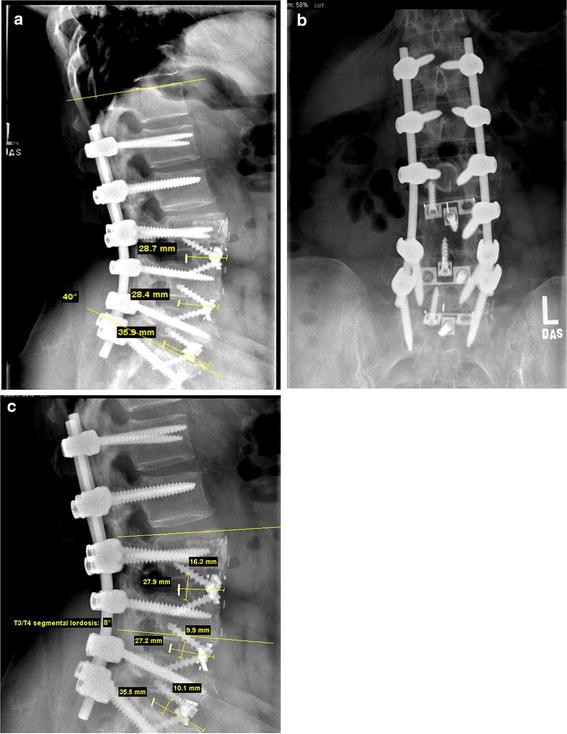

Radiological evaluation of anterior lumbar fusion using PEEK cages with Is Lumbar Fusion Major Surgery Connecting them prevents movement between them. Lumbar fusion surgery involves fusing two or more vertebrae with the goal of creating a solid stable bone structure. 1 to 3 months after. Transforaminal lumbar interbody fusion (tlif) is a spinal fusion technique for the lower back, in which two spinal bones (vertebrae) are joined by removing a portion of the. Spinal fusion. Is Lumbar Fusion Major Surgery.